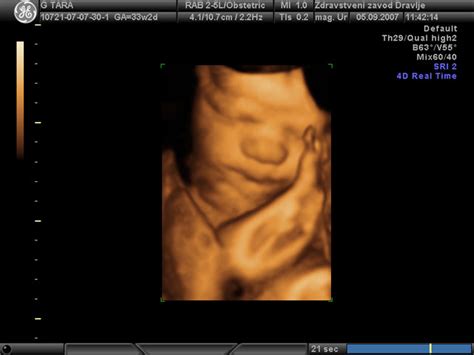

Ultrazvočni pregled je v sodobni medicini ključno orodje za spremljanje razvoja ploda, vključno z določanjem spola. Vendar pa, kot kažejo številne izkušnje, ta metoda ni povsem brez napak. Razlogov za napačno napoved spola je več, od tehničnih omejitev do anatomskih posebnosti otroka.

Ena izmed pogostih napak se pojavi, ko ultrazvok pokaže "lulčka", ki ga v resnici ni. To se lahko zgodi, kadar je popkovnica ovita med nogami otroka, kar na ultrazvočnem posnetku lahko spominja na moške spolne organe. V takih primerih je napoved o fantku lahko napačna. Podobno se lahko zgodi, da so ženski spolni organi obdani z vašimi hormoni, kar lahko povzroči njihovo povečanje in na ultrazvoku ustvari videz "lulčka", čeprav gre za deklico.